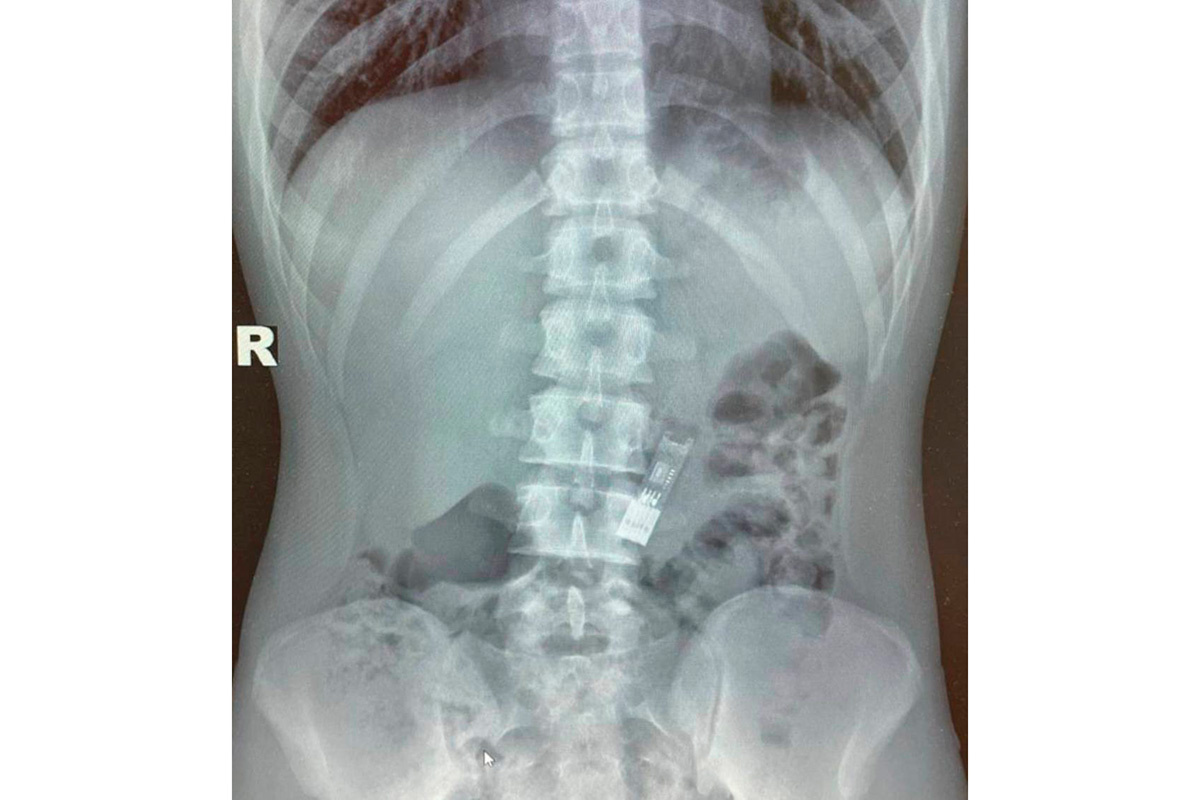

Врачи Детского клинического центра им. Л.М. Рошаля вытащили флешку с домашним заданием по информатике из желудка 16-летнего подростка, сообщает пресс-служба минздрава Московской области.

Молодой человек выполнил задание по информатике и загрузил его на флешку, после чего решил поиграть и начал крутить флешку перед лицом — и в какой-то момент проглотил цифровой носитель. Молодой человек понадеялся, что флешка выйдет естественным путем, но этого не случилось. Семья решила обратиться за помощью к врачам. Специалисты с помощью рентгенографии подтвердили, что флешка действительно оказалась в желудке.

«В условиях операционной мы провели мальчику наркоз и подготовили его к операции. С помощью специальных эндоскопических щипцов без единого разреза извлекли флешку из желудка. Процедура длилась всего 15 минут и прошла успешно», — рассказала лечащий врач-эндоскопист Дарья Степаненко.